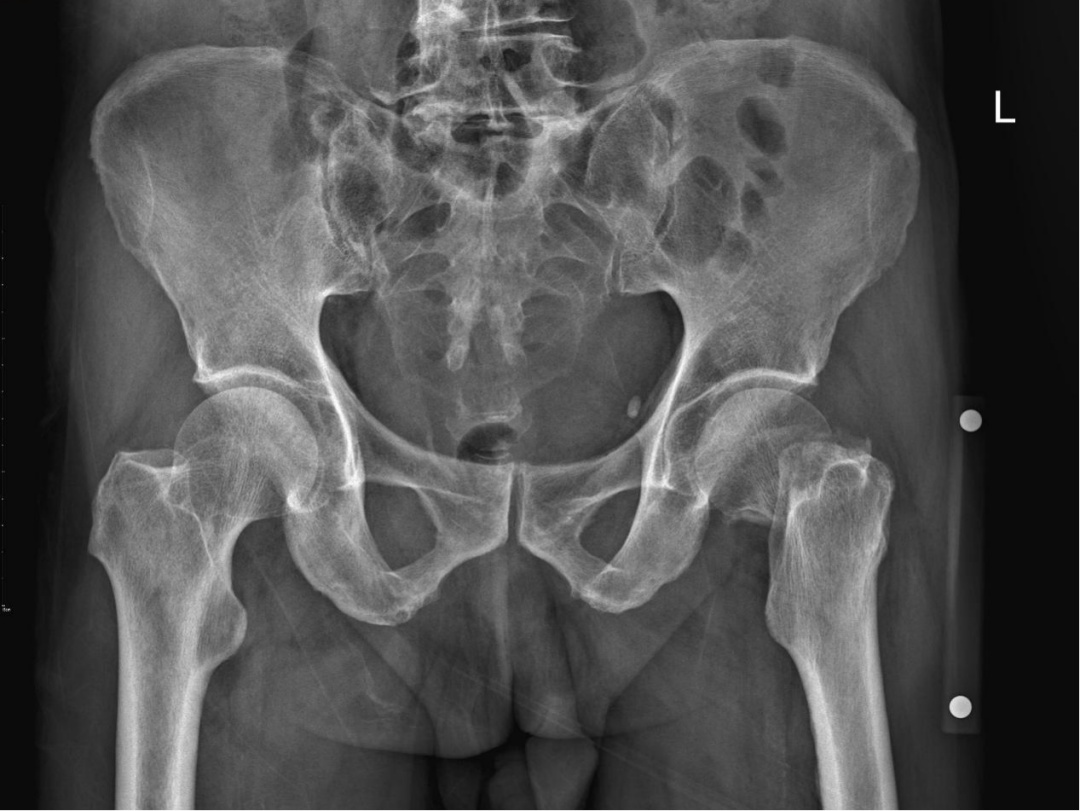

(术前骨盆X线片)

不日,肺动脉CTA(CT血管造影)的术前复查结果出来了:右肺动脉及左肺下叶动脉多处栓塞;同时,冠状动脉CTA回报:冠脉三支病变,左前降支近中段管腔中度狭窄,余管腔轻度狭窄。